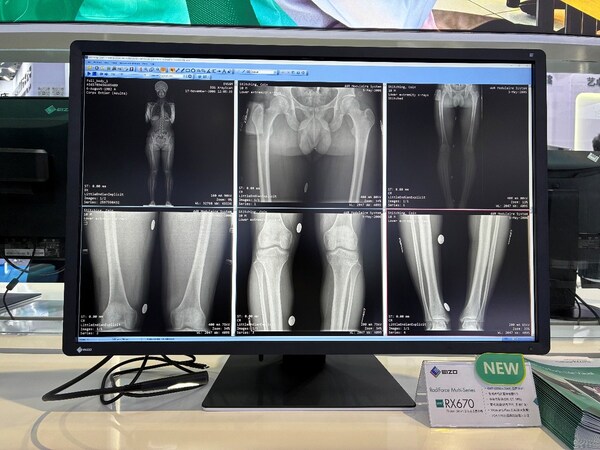

国内首发的艺卓RadiForce RX670医用显示器同台亮相,该产品拥有30英寸600万像素分辨率彩色液晶屏幕,显示器带有DICOM® Part 14校准功能,能够准确显示诊断影像,配合多模态显示功能,可同时展示胸部X光、CT、内窥镜、超声等多种检查影像,布局自由度高,有助于提升阅片效率。该设备还拥有Hybrid Gamma PXL功能,实现灰阶与彩色影像精准同屏显示。同时,该显示器采用USB Type-C®连接,可用于显示视频、传输USB信号、为连接的移动工作站供电,甚至传输网络信号,还可以通过简单的菊式链接轻松实现多屏设置,有助于远程工作时更快、更方便地连接到移动工作站。